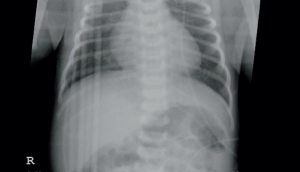

A 24-year-old G2P1001 African American female at 38.2 weeks of gestation was induced for labor for a fetus with prenatally diagnosed intrauterine growth restriction (IUGR). She subsequently delivered via normal spontaneous delivery. The infant initially latched well at the breast, was normoglycemic and normothermic, but shortly after birth had had a significant episode of blood-tinged emesis (not deemed to be swallowed maternal blood) and was transferred to the transitional nursery for further evaluation.